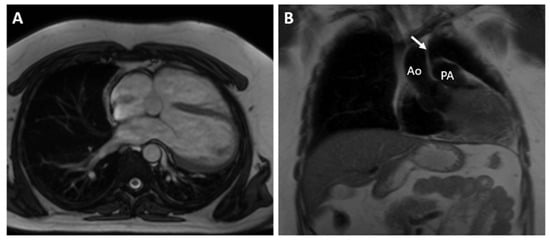

The CMR confirmed the abnormal position of the heart in the left hemithorax with laterally and posteriorly displaced apex and interposition of the lung tissue between the aorta and pulmonary trunk. There was no detectable pericardium overlying the left ventricular wall, and only a small discontinuous segments of pericardium were visualized surrounding the right atrium and right ventricular lateral wall (Figure 3 and Figure 4). Biventricular volumes and function were in the reference range. Additionally, a patent foramen ovale was visualized with no significant left-to-right shunt (Qp/Qs = 1.1).

Figure 4. SSFP CINE image in four chamber view (A) and T1-weighted fast spin-echo in axial view (B) demonstrate discontinuous segments of pericardium surrounding the right atrium and right ventricular lateral wall. No detectable pericardium was found around the left ventricular wall.

In patients with CAP, the history and physical examination are often nonspecific and with no role in making the diagnosis. The ECG is usually normal in small or partial defects. In cases with complete pericardial absence, some typical findings include right axis deviation, complete or incomplete right bundle block and sinus bradycardia induced by vagal stimulation [7]. In these cases, chronic lung disease, congenital interventricular and interatrial septal defects with hemodynamically significant shunts should be considered. Echocardiography is also not characteristic, but some findings may raise the clinical suspicion of this diagnosis. They include unusual acoustic windows due to the abnormal heart position, right ventricle dilatation, cardiac hypermobility, “teardrop” appearance, and paradoxical motion of the interventricular septum [8]. In our case, a dilated right ventricle was registered at TTE, and in the presence of atrial septal defect (ASD), we referred the patient for CMR. Our differential diagnosis was for a significant left–right shunt. Chest X-ray finding in complete pericardial absence is known as “Snoopy sign” and include combination of levoposition of the heart, elongation and flattening of the left heart border, radiolucency between the pulmonary artery and aorta due to interposition of lung tissue and loss of the right heart border [7]. In the past, a diagnostic left pneumothorax has been used to confirm the diagnosis showing pneumopericardium [9]. Nowadays, the imaging modalities of choice for detecting pericardial absence are computed tomography and cardiac magnetic resonance. Since they are not affected by the acoustic window, they have a better sensitivity in identifying the levoposition of the heart and lung interposition in the aorto-pulmonary window and between the inferior cardiac border and the diaphragm. CMR is the gold standard for evaluating the cardiac anatomy, volumes and function and can demonstrate any functional abnormalities or regional bulging and herniation of the heart associated with pericardial agenesis. CT, on the other hand, has a greater spatial resolution and can be of help in identifying small defects [10,11].